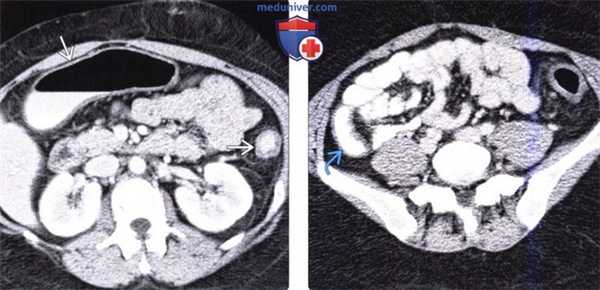

(Слева) На аксиальной КТ с контрастным усилением у женщины с язвенным колитом и первичным склерозирующим холангитом определяется распространенный фиброз ободочной кишки и отсутствие поперечных складок, из-за чего кишка приобрела вид «свинцовой трубы». Однородная структура утолщенной стенки ободочной кишки, имеющей низкую плотность, свидетельствует о длительно текущем заболевании.

(Справа) На аксиальной КТ с контрастным усилением у этой же пациентки определяется утолщение стенки дистальных отделов терминальной части подвздошной кишки, что расценивается как восходящий илеит. Язвенный колит имеет выражен ную взаимосвязь с первичным склерозирующим холангитом.

(а) На поперечном КТ-срезе (КТ-энтерография) после введения перорального и внутривенного контраста определяется стратификация слоев стенки и выраженная неравномерность оставшихся сохранными участков слизистой оболочки на фоне множественных язв (указатели) в поперечной ободочной кишке.

(б) На корональной КТ (реформатированное изображение, КТ-энтерография) определяется воспалительный псевдополипоз (стрелки) с распространением в просвет печеночного изгиба ободочной кишки.

В острой стадии зернистость слизистой оболочки, которая обусловлена ее отеком, гиперемия и патологическая секреция муцина являются самыми ранними рентгенологическими признаками при ирригоскопии с двойным контрастированием (ИДК). При увеличении выраженности воспалительных изменений на КТ может обнаруживаться протяженное и симметричное утолщение стенки кишки с наличием симптома «гало» (с плотностью воды). Изъязвление слизистой оболочки и подслизистой основы с распространением латерально в подслизистом слое приводит к возникновению типичных язв в виде «пуговицы на воротнике» при ИДК.

На фоне выраженного изъязвления некоторые участки слизистой оболочки остаются нетронутыми, обусловливая изменения в виде воспалительного псевдополипоза, которые могут быть обнаружены как на КТ при хорошем растяжении ободочной кишки, так и при ирригоскопии с двойным контрастированием. В хронической стадии на КТ обычно определяется утолщение стенки кишки с наличием «гало» (помутнение окружающей жировой клетчатки), сужение просвета кишки и расширение пресакрального пространства из-за гипертрофии мышечной пластинки слизистой оболочки, отложения жира в подслизистой оболочке и околопрямокишечной области. При ирригоскопии с двойным контрастированием просвет пораженной ободочной кишки выглядит суженным, кишка лишена гаустр и укорочена; часто наблюдается также поствоспалительный псевдополипоз (патологическая пролиферация воспаленной слизистой оболочки (Gore et al., 1996; Lichtenstein, 1987).